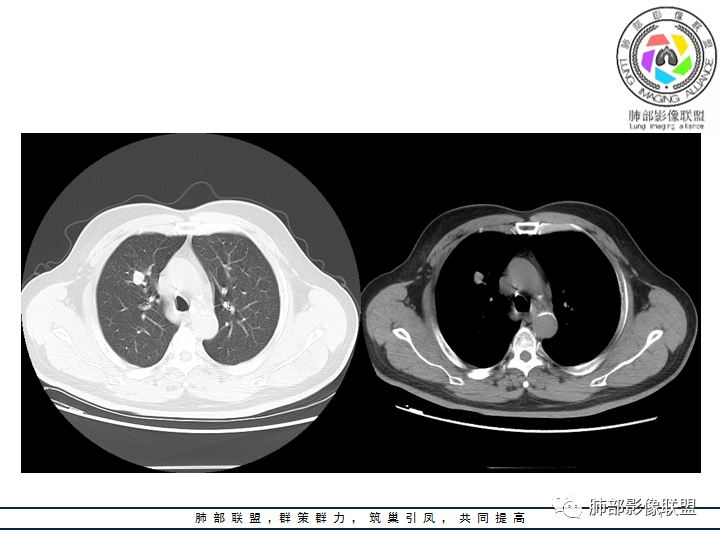

老年男性患者,长期吸烟史,没有呼吸系统临床表现。胸部CT示右肺上叶实性密度结节影,密度均匀,未见空洞及钙化,边缘较光整,未见分叶及毛刺。血管影旁现侧出,支气管进入并截断,不均匀强化。

影像上结节影或块影一旦与支气管密切相关(如截断),不支持硬化性肺细胞瘤、错构瘤、孤立性纤维瘤等良性病灶。如此清晰的边缘也不符合一般意义上的炎性渗出。

刘海玲:右肺上叶实性结节,边缘有分叶,增强后有强化。考虑恶性,腺癌可能。

张丽:右肺上叶实性结节,边缘膨隆分叶,增强后有强化,考虑恶性,腺癌,鉴别类癌。